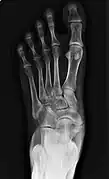

Images radiologiques

De gauche à droite : types 1, 2 et 3

Os naviculaire cornéen